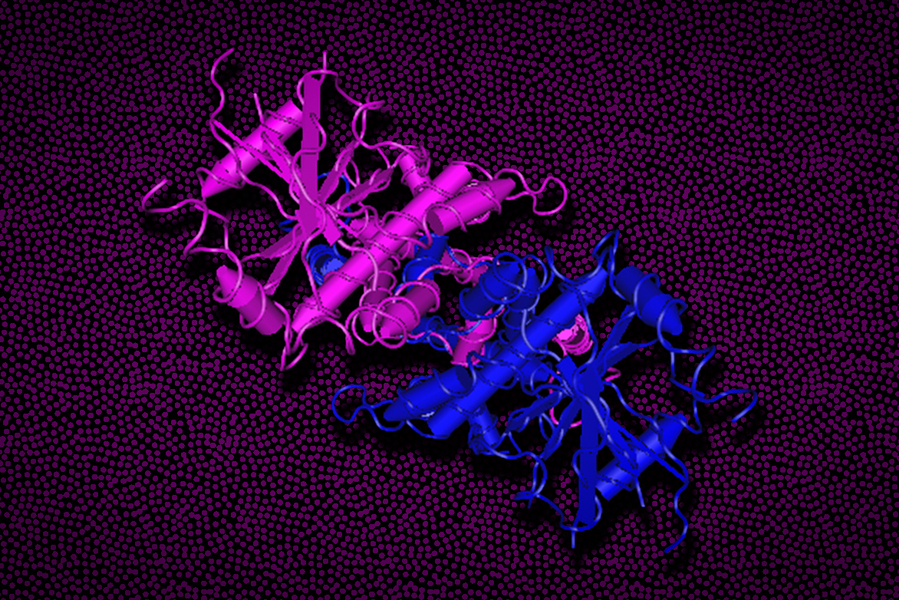

医療・健康 主要な免疫制御因子の驚くべき新役割を発見(Study finds a surprising new role for a major immune regulator)

STINGタンパク質は、細胞防御に関わる遺伝子のスイッチを入れるだけでなく、イオンチャネルとしても働き、さまざまな免疫反応を制御することができる。In addition to turning on genes involved in cel...